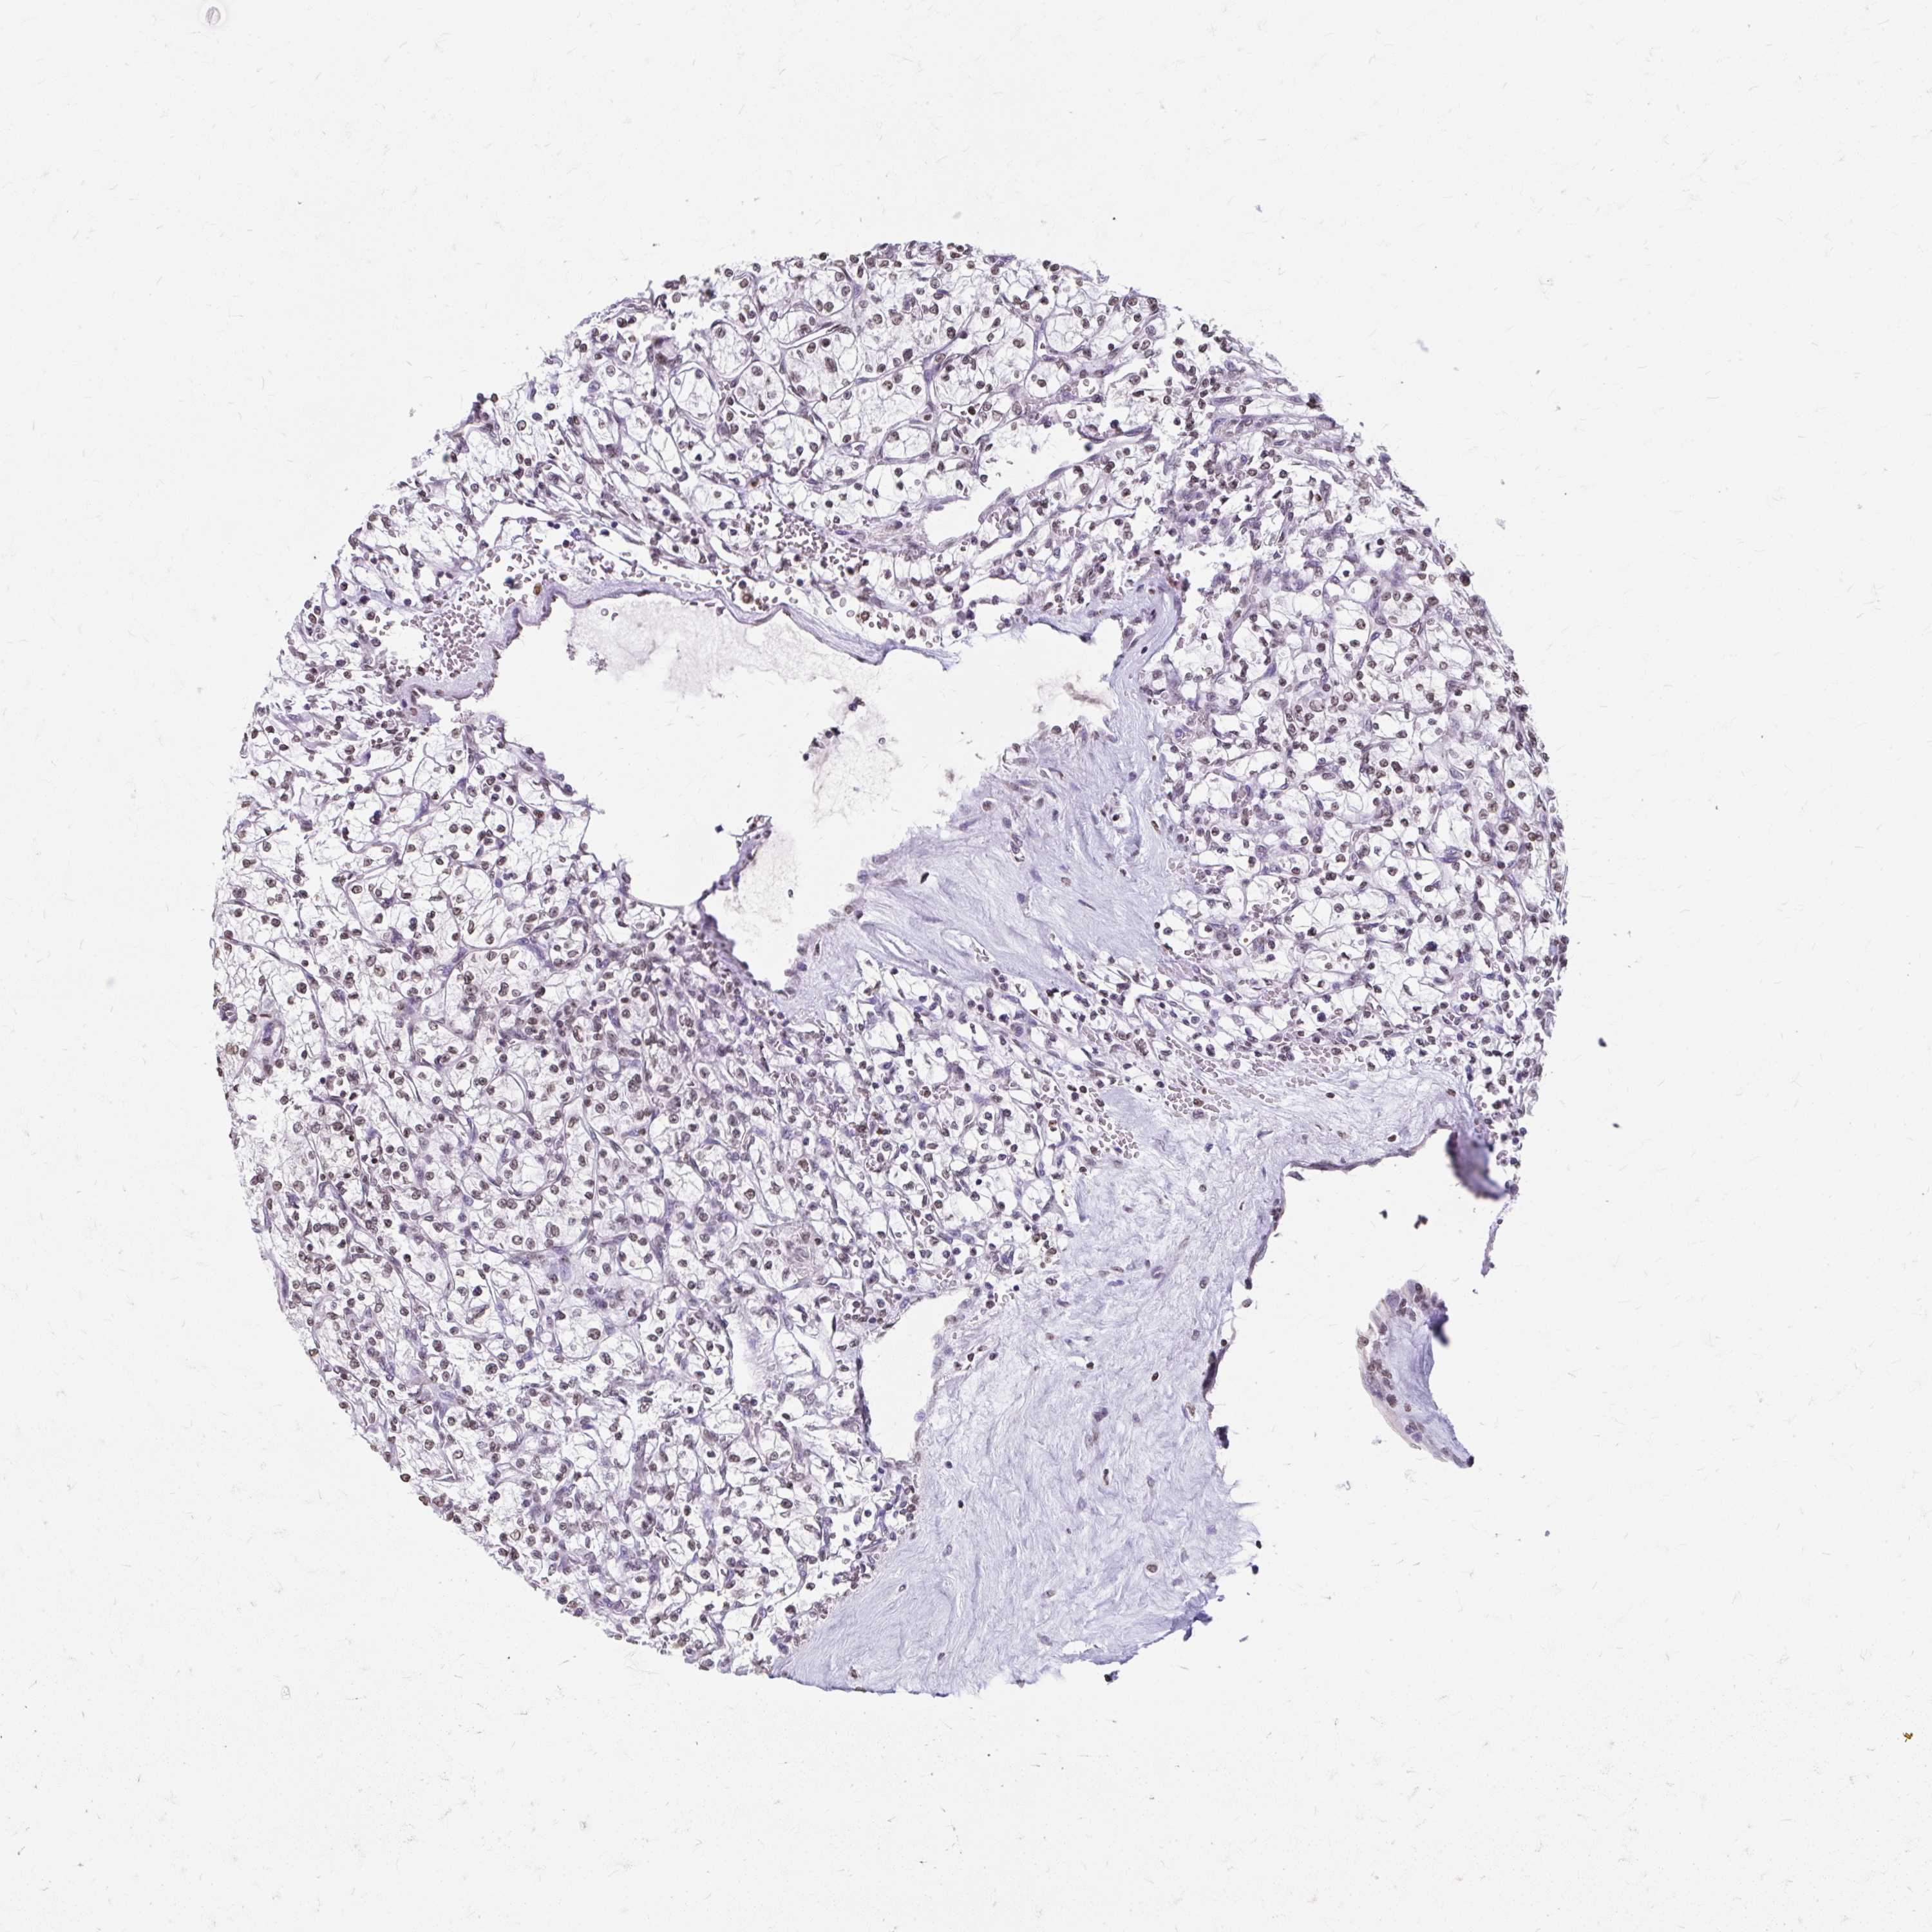

KIDNEY RENAL CLEAR CELL CARCINOMA (VALIDATION) - Interactive survival scatter ploti

The Survival Scatter plot shows the clinical status (i.e. dead or alive) for all individuals in the patient cohort, based on the same data that underlies the corresponding Kaplan-Meier plots. Patients that are alive at last time for follow-up are shown in blue and patients who have died during the study are shown in red.

The x-axis shows the expression levels (FPKM) of the investigated gene in the tumor tissue at the time of diagnosis. The y-axis shows the follow-up time after diagnosis (years). Both axes are complimented with kernel density curves demonstrating the data density over the axes. The top density plot shows the expression levels (FPKM) distribution among dead (red) and alive patients (blue). The right density plot shows the data density of the survived years of dead patients with high and low expression levels respectively, stratified using the cutoff indicated by the vertical dashed line through the Survival Scatter plot. This cutoff is automatically defined based on the FPKM cutoff that minimizes the p-score. The cutoff can be changed by dragging the vertical line or by entering a cutoff value in the square labeled "Current cut-off".

Under the Survival Scatter plot the p-score landscape (black curve; left axis) is shown together with dead median separation (red curve; right axis). Dead median separation is the difference in median mRNA expression between patients who have died with high and low expression, respectively. It is calculated as follows: median FPKM expression of dead patients with high expression - median FPKM expression of dead patients with low expression. This is intended to aid the user in visually exploring custom cutoffs and the associated p-scores and dead median separation.

Individual patient data is displayed and can be filtered by clicking on one or more of the category buttons on the top of the page. Categories describing expression level and patient information include: high, low, alive, dead, female, male and tumor stages. The scale of the x-axis can be toggled between linear and log-scale by clicking on the "x log" button. Mouse-over function shows TCGA ID, patient information and mRNA expression (FPKM) for each patient.

& Survival analysisi

Kaplan-Meier plots summarize results from analysis of correlation between mRNA expression level and patient survival. Patients were divided based on level of expression into one of the two groups "low" (under cut off) or "high" (over cut off). X-axis shows time for survival (years) and y-axis shows the probability of survival, where 1.0 corresponds to 100 percent.

ORC3 is not prognostic in Kidney Renal Clear Cell Carcinoma (validation)

Best expression cut offi

Based on the FPKM value of each gene, patients were classified into two groups and association between prognosis (survival) and gene expression (FPKM) was examined. The best expression cut-off refers the FPKM value that yields maximal difference with regard to survival between the two groups at the lowest log-rank P-value. Best expression cut-off was selected based on survival analysis .

When clicking on this number, the vertical dashed line indicating cut-off, the interactive survival plot, and the Kaplan-Meier curve will be adjusted to show results based on the best expression cut-off.

: 15.73

P scorei

Log-rank P value for Kaplan-Meier plot showing results from analysis of correlation between mRNA expression level and patient survival.

N/A

TCGA RNA samplesi

RNA-seq data is reported as average FPKM (number Fragments Per Kilobase of exon per Million reads), generated by the The Cancer Genome Atlas (TCGA) .

Normal distribution across the dataset is visualized with box plots, shown as median and 25th and 75th percentiles. Points are displayed as outliers if they are above or below 1.5 times the interquartile range. FPKM values of the individual samples are presented next to the box plot.

Average pTPM 18.3

Number of samples 100